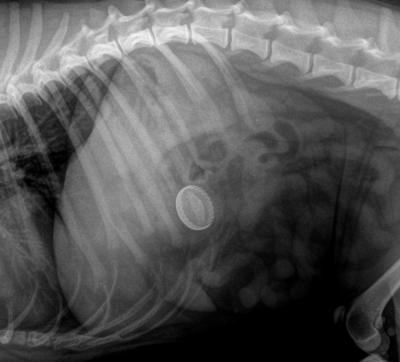

RTG břicha pejska, co pomáhal při zdobení dortu.

Podrobněji zpracovaný případ prvního pacienta. Majitel se dostavil s tím, že jim pes pravděpodobně snědl zdobící pytlík i se zdobičkou. A aby toho nebylo málo, tak jim ještě vyhrabal koš. Bylo provedeno RTG vyšetření, které potvrdilo obavy majitele.

V žaludku bylo kromě zdobičky s pytlíkem i velké množství granulí a slupky ze dvou banánů.

Po otevření dutiny břišní byl žaludek vybaven do operační rány a fixován pomocnými stehy. Tyto stehy umožňují přidržet okraje žaludeční stěny a zabránit úniku agresivních žaludečních šťáv do břišní dutiny. Po zarouškování byla stěna žaludku protnuta (viz foto) a byla započata evakuace žaludečního obsahu.

Uzávěr stěny žaludku pomocí dvojité etáže.

Předmět doličný o celkové délce 20 cm. Ostré hrany kovové zdobičky ve spojení s dlouhým plátěným pytlíkem vylučují spontánní průchod střevem, ale i možnost vyzvracení. Proto bylo nutné chirurgické řešení.